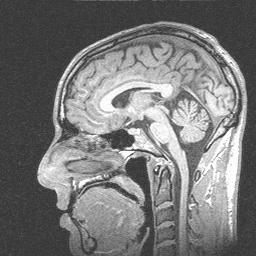

During the summer of 2000, I participated in an fMRI (functional magnetic resonance imaging) study at the University of Virginia.  An fMRI scan shows not only the structure of the brain, but which parts are currently active.  By asking people to do different things while being scanned, psychologists are able to figure out which parts of the brain are used for different tasks.

Since I was working with the psychologists at the time, I was not paid to participate in the study.  However, I volunteered to do it anyway in order to help out my friends, advance mankind's knowledge, and get really cool pictures of what my brain would look like if my head were chopped in half.  Enjoy!

Sagittal view